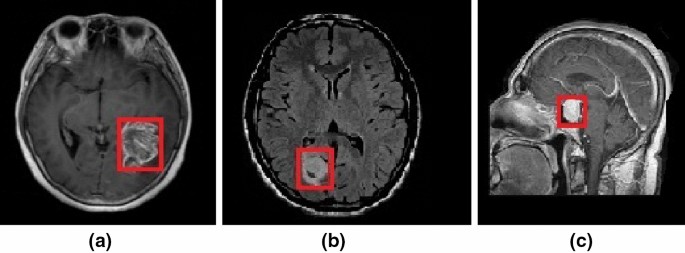

Case Report Predominant Brain Superficial Location F1000research